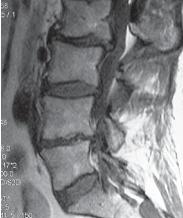

Чтобы вы лучше понимали, как выглядит позвоночник когда в позвоночном сегменте уже нет диска и происходят вышеупомянутые процессы фибротизации и васкуляризации (относящиеся к последней стадии развития дегенеративно-дистрофического процесса), приведу ещё один снимок пациента после многократных хирургических вмешательств. МРТ № 102 ![]() На МРТ № 102 хорошо видно, как после многократных хирургических вмешательств образуется множество послеоперационных рубцов, спаек и других проблем в позвоночнике. То есть, созданы все условия для фибротизации (перерождения ткани диска, образования фиброзных волокон) и васкуляризации (лат. vas — сосуд; формирования новых капилляров, в данном случае при процессе сращивания костной ткани). Всё это способствует сращиванию двух смежных тел позвонков, лишённых диска. В свою очередь это исключает подвижность в данном сегменте, приводит к стенозу фораминальных отверстий (как вы помните, это отверстия, через которые проходят нервные корешки и сосуды). Вдобавок ко всему, послеоперационные спайки и рубцы в спинномозговом канале могут способствовать развитию воспалительных процессов, о которых уже упоминалось выше. Нарушение функциональной способности данного позвоночного сегмента ведёт к ещё большим биомеханическим нарушениям в позвоночнике, соответственно частичной утрате его рессорных свойств, а следовательно, значительному снижению сопротивляемости к разнообразным вертикальным нагрузкам. Как правило, в таких случаях, когда межпозвонковый диск безвозвратно утрачен или при наличии «необратимых изменений анатомической структуры межпозвонковых дисков», хирурги предлагают сделать другую операцию с использованием ортопедических методов оперативного лечения (тотальная дискэктомия с межтеловым спондилодезом). Дискэктомия (discectomia; discus intervertebralis — межпозвонковый диск; ectomia от греч. ektome — вырезание, иссечение, удаление) — хирургическая операция удаления межпозвонкового диска. Спондилодез (spodylodesis; от греч. spodylos — позвонок, desis — связывание) — операция, направленная на обездвижение какого-либо сегмента или отдела позвоночника; межтеловой спондилодез — хирургическое соединение тел позвонков по типу слияния. Данная операция предусматривает полное (тотальное) удаление дегенерирующего межпозвонкового диска и последующее его замещение имплантантом (неподвижной или подвижной конструкции, хотя разница по последствиям невелика). Естественно, после такой операции рецидива грыжи межпозвонкового диска в данном сегменте просто не может быть, так как нет и самого диска (но это не исключает грыжеобразование в других сегментах позвоночника вследствие нарушения его биомеханики). Основной целью данной операции является сохранение высоты дискового промежутка и размеров межпозвонковых отверстий. Конечно, живой диск это не заменит и полноценной функциональной подвижности в данном сегменте также не вернёт (соответственно, всего лишь незначительно стабилизирует нарушенную работу мышц, связок). Безусловно, глобально это проблемы позвоночника не решит, поскольку биомеханические нарушения в позвоночнике по-прежнему будут иметь место. Как говорится, одно звено сломано — вся цепь порвана. Следующий пример показывает состояние поясничного отдела позвоночника через два года после проведённой ламинэктомии. Ламинэктомия (лат. lamina — пластинка, греч. ektome — иссечение) — хирургическая операция: вскрытие позвоночного канала путём удаления дуг позвонков. МРТ № 103

На МРТ №°103 наблюдается грыжа межпозвонкового диска в сегменте LIV-LV, частично компенсированная спондилёзом, гипертрофия задней продольной связки и выраженный эпидурит на данном уровне. В сегменте LV-SI наблюдается протрузия межпозвонкового диска, компенсированная спондилёзом. На уровне этих же сегментов наблюдается рубцовоспаечный процесс, как следствие перенесённой хирургической операции — ламинэктомии, проведённой в сегментах (LIV-LV, LV-SI), с целью устранения грыжи межпозвонковых дисков и декомпрессии спинномозговых корешков на данных уровнях. Приведённый ниже случай является показательным примером, как пациентка попала к недобросовестному хирургу, который сделал ей абсолютно необоснованную операцию. ![]() На МРТ № 104 наблюдается начальная стадия дегенеративного процесса в шейном отделе позвоночника, протрузия межпозвонкового диска в сегменте CVI—CVII. На МРТ № 105 наблюдается состояние после проведённой тотальной дискэктомии с передним межтеловым спондилодезом в сегменте CV—CVII, выпрямление физиологического лордоза, абсолютный стеноз спинномозгового канала с блоком ликворных путей, секвестрированные грыжи (с краниальной миграцией секвестров) в сегментах CIV-CV, CV-CVI, CVII-ThI. Состояние пациентки после операции ухудшилось, а в течение последующего года — значительно усугубилось. В данном конкретном случае не совсем понятно, зачем сделали эту операцию? Дооперационные жалобы больной были больше сосудистого характера. Прямых показаний к операции просто не было! Если бы данная пациентка прошла медикаментозное лечение у невропатолога, без хирургического вмешательства, то сейчас её здоровье было бы намного лучше, да и будущее бы не вызывало опасений в плане последующих осложнений. Вот ещё трагический случай во время проведения необоснованной операции. ![]() На МРТ № 106 состояние шейного отдела пациентки до операции. Наблюдается сглаженность физиологического лордоза, ликворные пути свободны, компенсированные протрузии межпозвонковых дисков в сегментах СIII—СIV На МРТ № 107 состояние шейного отдела той же пациентки после дискэктомии с межтеловым спондилодезом в сегменте CV—CVI, кроме того наблюдается травма спинного мозга на данном уровне хирургической фрезой. Если до операции у данной пациентки были незначительные вертебробазилярные нарушения, то после… Травма спинного мозга хирургической фрезой — это, конечно, трагическая случайность. Ведь от ошибок никто не застрахован и добросовестный врач никогда не даст гарантии на положительный исход любого вида лечения. Но в данном случае проведение самой операции было абсолютно необоснованным, фактически она превратила нормального человека в инвалида. Следующий пример также демонстрирует, какие бывают последствия после дискэктомии с межтеловым спондилодезом. |